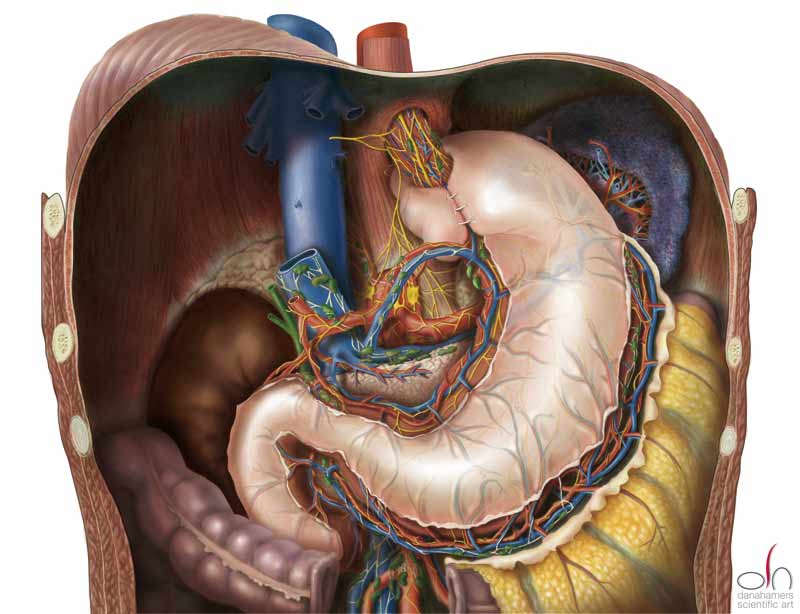

A completed Nissen fundoplication

By Dana Hamers - Own work, CC BY-SA 3.0, https://commons.wikimedia.org/w/index.php?curid=20453728